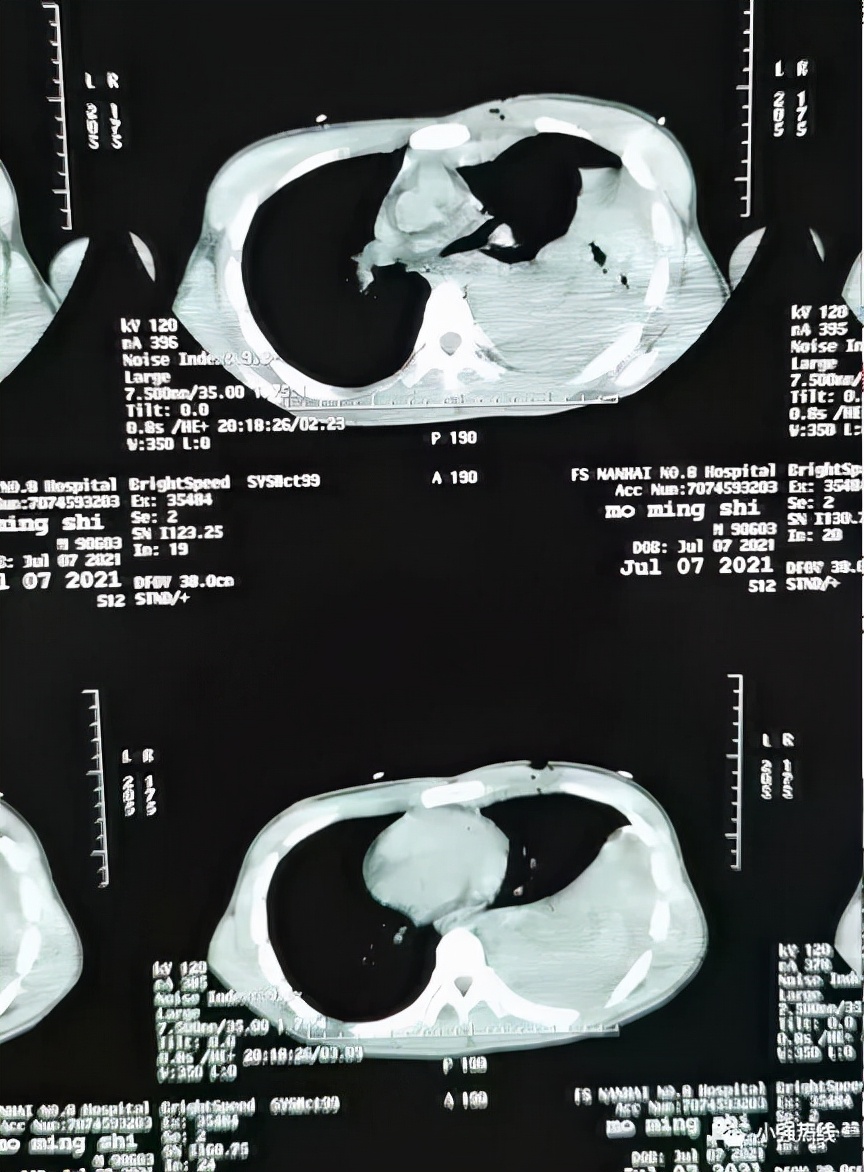

据当晚参与抢救的医生回忆,当时小明身上 插着刀长20厘米 , 刀尖甚至刺穿背部,失血达3500毫升,已进入休克状态 。经检查,小明失血性休克、动脉破裂、开放性气血胸、开放性肺破裂。3500毫升血液,占人体总血量70%,生死一线间,倘若再晚一点,后果不堪设想!

与生死竞速,创伤团队的专家医生们迅速制定好手术方案,为小明开胸止血,做肺部修补术、胸腔闭式引流术,经过 一个半小时的抢救 ,小明手术成功被送入ICU观察。